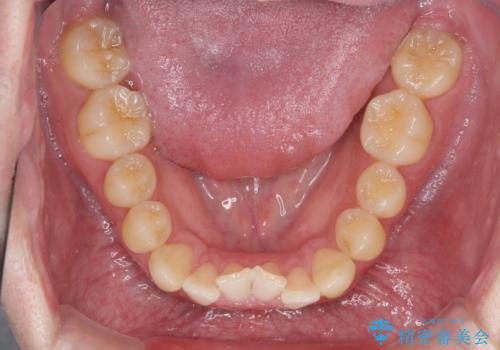

前歯のクロスバイト インビザラインによる矯正治療

- 上下のクロスバイトと前歯のデコボコを気にして来院された患者様です。

インビザラインを用い、IPR(歯と歯の間を削る)と歯列全体を拡大させることで、歯並びを整えていくこととしました。

奥に位置していた上の前歯が下の前歯を乗り越える際、奥歯でものを咬むことができず、辛い時期が続きました。